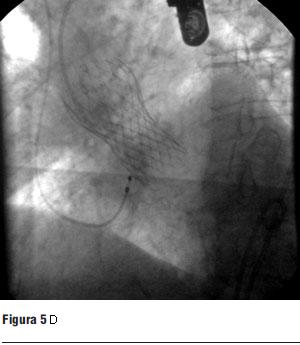

Visto el caso en ateneo médico quirúrgico y en conjunto con el paciente, dado que fue intervenido con cirugía de revascularización miocárdica en dos oportunidades, se decide evaluar la factibilidad del implante percutáneo de válvula aórtica para lo cual se realizó angiotomografía de aorta y miembros inferiores con tomógrafo multicorte de 16 filas de detectores. Se realizaron reconstrucciones 3D de aorta toracoabdominal y estudio con contraste. Dicho estudio mostró aorta con múltiples calcificaciones parietales sobre todo en aorta ascendente próxima a la válvula y valvulares, en cayado y aorta abdominal, sin disección. Diámetro de aorta en su origen 31 mm, aorta ascendente 26 mm. Sin estenosis en arterias del cuello; aorta abdominal de calibre habitual; arterias ilíacas y femorales de calibre habitual y sin imágenes de estenosis. Diámetro del anillo: 24 mm, altura del sinus: 15.5 mm, diámetro de raíz de aorta: 30,0 mm, arteria femoral izquierda: 8,6 mm, arteria femoral derecha: 8,4 mm (figura 1).

Figura 1. Angiotomografía (AngioTC) de aorta y miembros inferiores. Las imágenes blancas en placas corresponden a calcificaciones.